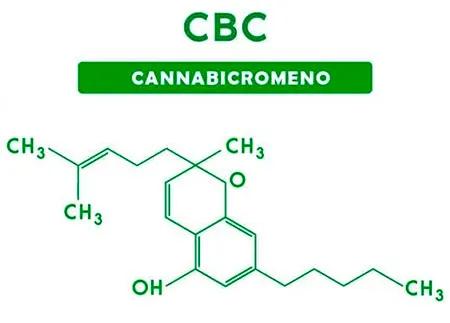

Estructura química del Cannabicromeno (CBC).

La noticia volvió a poner el foco sobre un cannabinoide menos transitado: el cannabicromeno (CBC). A diferencia del CBD o el THC, el CBC suele quedar fuera del radar mediático, aunque aparece con frecuencia en perfiles químicos de planta completa. En este trabajo, no se ensayaron moléculas aisladas sino extractos con composiciones distintas, confirmadas por cromatografía (HPLC), donde el CBC y el delta-9-tetrahidrocannabinol figuraron como componentes relevantes.